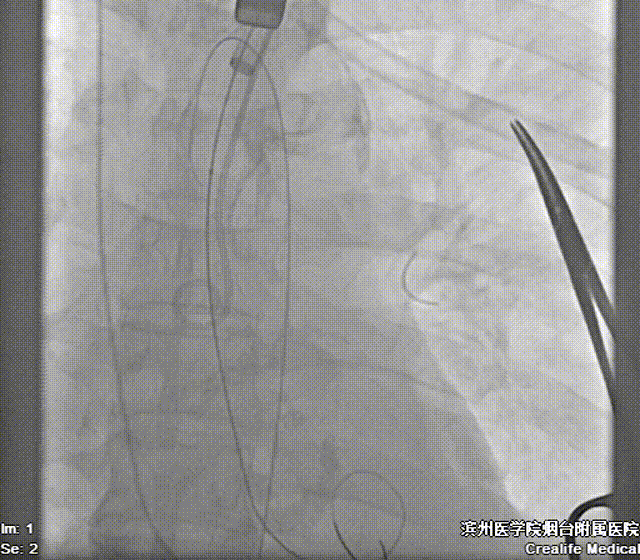

术前测量,患者主动脉峰值流速452cm/s,平均跨瓣压差36mmHg,术中通过患者左侧锁骨下动脉建立辅入路,造影示主动脉根部明显钙化,左室内中量反流影像。

右侧股动脉入路建立后,在双侧髂总动脉汇合处遭遇顽固钙化,器械无法向心推进,术中改以左侧腋动脉为主入路。

22mm球囊预扩影像示双侧冠脉灌注良好,无明显腰征,决定植入AV26号瓣膜。

造影辅助下精准释放